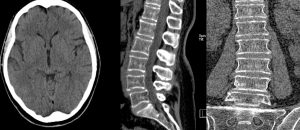

Tumore tac testa. Tumore al cervello (o tumore cerebrale) è un’espressione alquanto generica con la quale, oltre ai tumori che si originano nel cervello propriamente detto, si indicano anche le neoplasie che si sviluppano a livello del sistema nervoso centrale I tumori cerebrali sono considerati tumori rari, rappresentando poco più dell’1% di tutti i tipi di tumore. La TAC, acronimo di Tomografia Assiale Computerizzata, è una tecnica diagnostica che sfrutta le radiazioni ionizzanti (o raggi X) per ottenere immagini dettagliate, in versione tridimensionale, di aree anatomiche specifiche del corpo umano (es encefalo, ossa, vasi sanguigni, organi addominali, organi toracici, vie respiratorie ecc) La TAC è una procedura di radiologia;. Polmone degli organismi invertebrati Nonostante la maggior parte delle specie terrestri abbia adottato la respirazione tracheale, molti invertebrati hanno delle strutture polmonari, generalmente meno complesse Gli aracnidi come ragni e scorpioni presentano strutture atte allo scambio gassoso dette polmoni a libroI granchi usano strutture simili, dette branchiostegali che permettono anche la.

La TAC alla testa è di aiuto, principalmente, nella diagnosi delle malattie tumorali, vascolari o infettive che colpiscono l'encefalo, nello studio delle conseguenze dei traumi cranici e nell'individuazione delle malformazioni congenite a carico delle ossa craniche e di condizioni come l'idrocefalo Della durata totale di 30 minuti al massimo, la TAC alla testa prevede una certa preparazione. Nelle donne invece è meno comune, collocandosi al quarto posto per frequenza L’aumento dell’abitudine al fumo di sigaretta nel sesso femminile e la sua riduzione nel sesso maschile, ha determinato, tuttavia, una crescita di frequenza nelle donne ed una diminuzione.